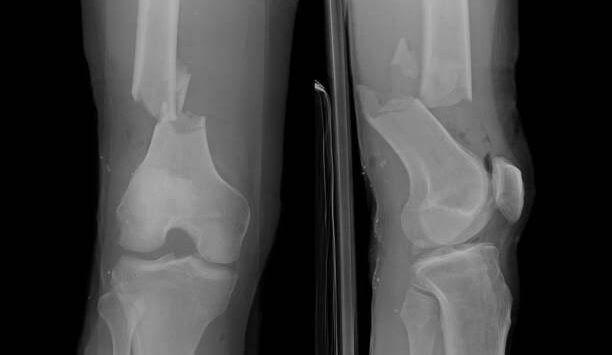

Comminuted fractures are a type of broken bone. The term comminuted fracture refers to a bone that is broken in at least two places. Comminuted fractures are caused by severe traumas like car accidents. You will need surgery to repair your bone, and recovery can take a year or longer.